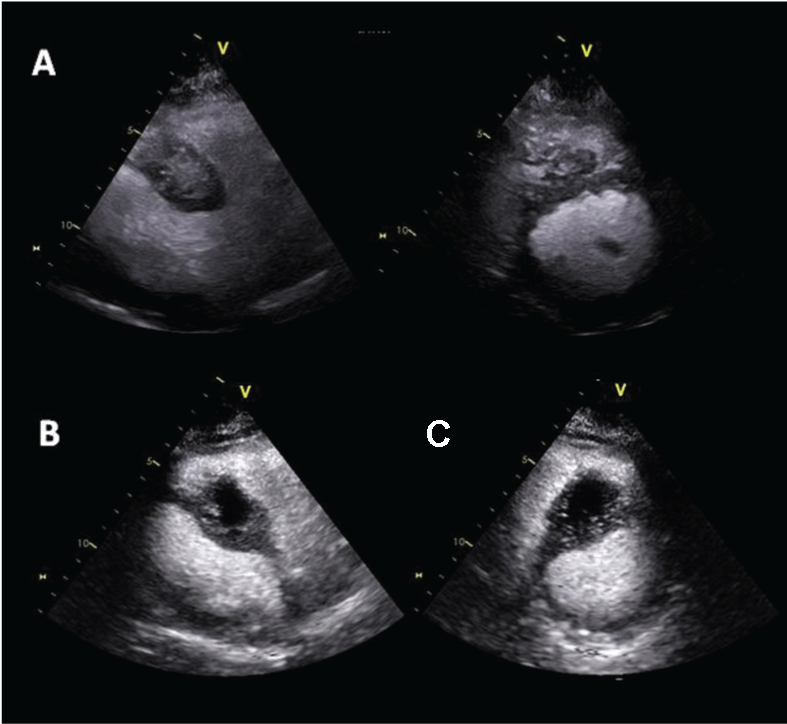

Transthoracic echocardiography confirmed the presence of a voluminous inhomogeneous mass within the interventricular septum jutting in the right ventricle (Figure 1). Contrast perfusion imaging was used for characterizing mass vascularization. Following a slow intravenous injection of a second generation contrast agent (Sonovue, Bracco, Milano, Italy) hyperintense inhomogeneous enhancement was attained (Figure 2).

Figure 1: (A) Two-dimensional (2D) echocardiography apical 4-chamber view; (B) Apical long axis view; (C) Short axis view. The interventricular septum appears thickened for the presence of a inhomogeneous infiltrating mass jutting in the right ventricle.

Figure 2: (A) Contrast echocardiography off axis and short axis views showing inhomogeneous contrast enhancement of cardiac carcinoid metastasis within the interventricular septum; (B) Contrast echocardiography showing the appearance of an area of hypoperfusion suggestive of partial necrosis of the mass.

Follow-up of the myocardial neoplastic lesion included serial standard and contrast echocardiography. Standard echocardiography showed a slow progressive growth of the mass mainly toward the right ventricle (26 mm × 35 mm). Contrast echocardiography evaluation demonstrated inhomogeneous perfusion of the mass with new appearance of an area of hypoperfusion suggestive of partial necrosis of the mass (Figure 2). A CMR confirmed these findings.

Echocardiographic evaluation evidenced the cardiac mass appearing inhomogeneous and infiltrating, not as previously described. Contrast echocardiography allowed for defining the metastasis profile, size measurement and growth monitoring during follow-up. This also showed its vascularization demonstrating hyperenhancement indicating neovascularization and a hypoenhanced area of partial necrosis (Figure 1 and Figure 2). We believe this is a novel case describing echo contrast features of a cardiac neuroendocrine tumor metastasis.